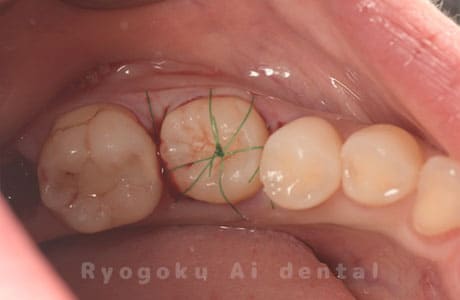

Case27

-

重度カリエス

歯牙移植咬合面術前 -

移植する親知らず

歯牙移植術直後咬合面

歯牙移植術後咬合面

歯牙移植術前側面

歯牙移植術中側面

歯牙移植術後側面

- 原因

- 重度カリエス

- 治療内容

- 自家歯牙移植、部分矯正

- 治療費用

- 220,000円(移植費用)

110,000円(部分矯正費用)

虫歯が大きく、保存不可能となった歯を上の親知らずと交換する自家歯牙移植を行いました。移植歯が小ぶりであったため、部分矯正を行い問題なく噛み合い、経過良好です。